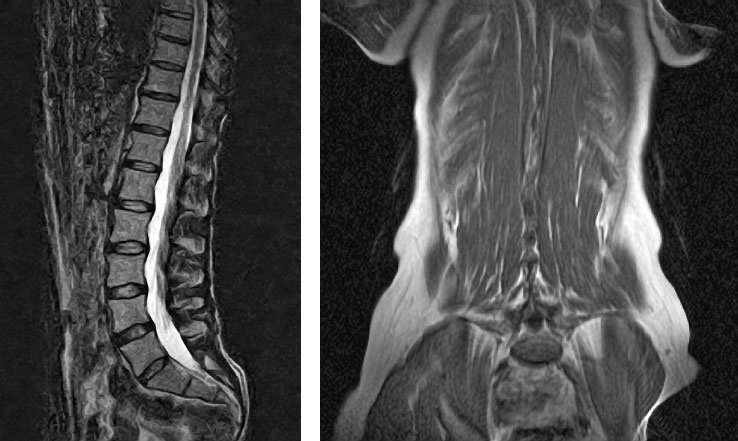

Рисунок 15. Нагрузка способствует повышению плотности кости. Йога компенсирует ущерб, причиненный повседневной деятельностью. Обратите внимание на прекрасный позвоночник этого практика и учителя йоги с 16-летним стажем.